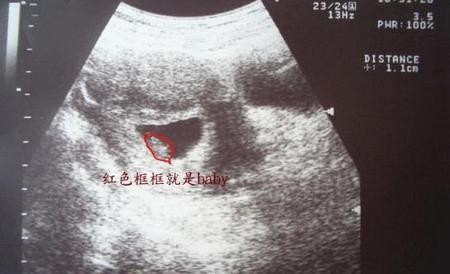

不同孕周,HCG数值不同,而且并不会随着孕周一直增加(具体范围如下图),检查结果要咨询医生,听医生的建议就好。